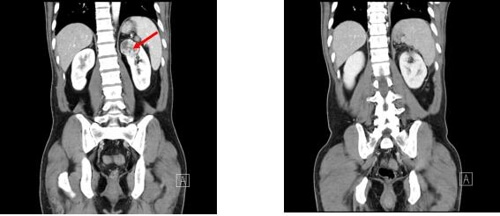

신장의 위치는 흉곽 깊은 위치에 있다고 해요. 신장이 안좋아지게 되면 신장이 위치한 허리 주변으로 통증을 유발할게 할 수 있어요. 그리고 사타구니 및 엉덩이 부위의 앞쪽에서도 통증이 생기게 될 우려도 하고 심할 경우, 고열을 일으키기도 하며 구토를 동반하기도 해요.

신장이 안좋으면 나타나는 증상11. 요통 또는 옆구리 통증

신장이 손상되거나 약해질 때 등, 옆구리 또는 복부에 통증이 생기게 될 수 있어요.